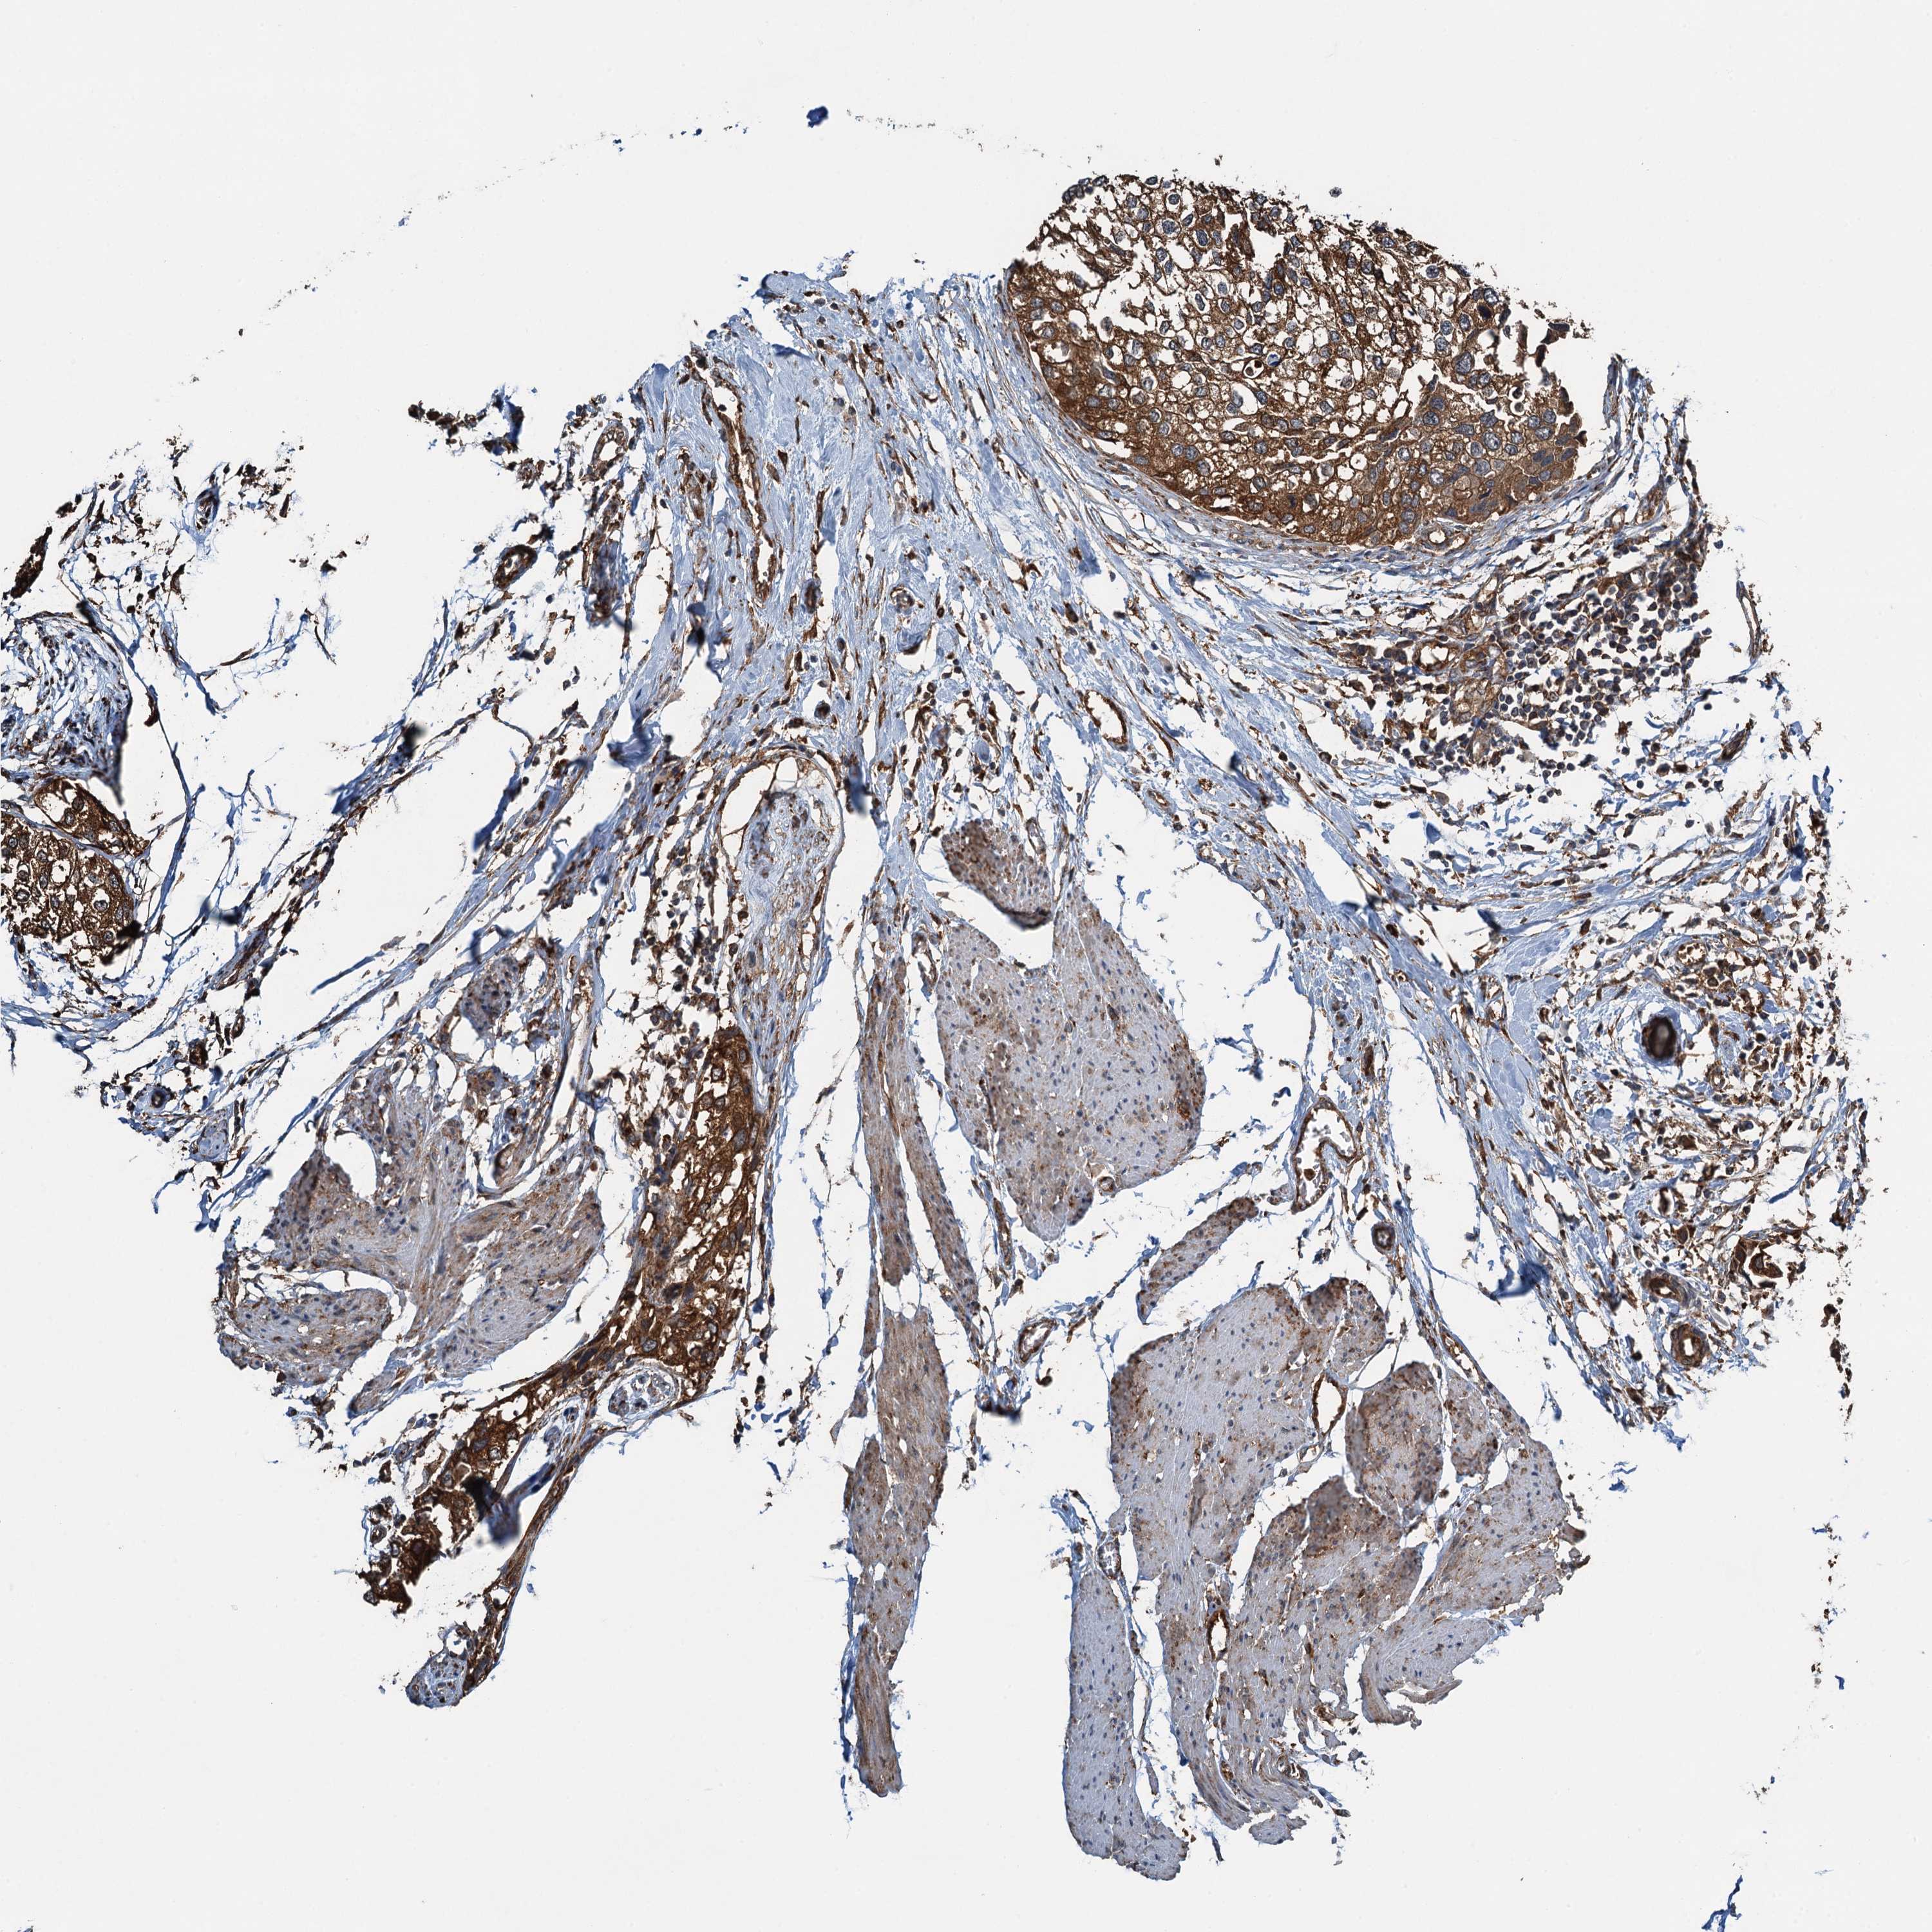

UROTHELIAL CANCER - Protein expressioni

A mouse-over function shows sample information and annotation data. Click on an image to view it in a full screen mode. Samples can be filtered based on level of antibody staining by selecting one or several of the following categories: high, medium, low and not detected. The assay and annotation is described here.

Note that samples used for immunohistochemistry by the Human Protein Atlas do not correspond to samples in the TCGA dataset.

Antibody stainingi

Antibody staining in the annotated cell types in the current human tissue is reported as not detected, low, medium, or high, based on conventional immunohistochemistry profiling in selected tissues. This score is based on the combination of the staining intensity and fraction of stained cells.

Each image is clickable and will lead to virtual microscopy that enables deeper exploration of all samples and also displays staining intensity scores, fraction scores and subcellular localization as well as patient and tissue information for each sample.

Antibody HPA039690

Antibody HPA040231

Staining

High

Medium

Low

Not detected

Intensity

Strong

Moderate

Weak

Negative

Quantity

>75%

75%-25%

<25%

None

Location

Nuclear

Cytoplasmic/membranous

Cytoplasmic/membranous,nuclear

Urothelial carcinoma, High grade

Urothelial carcinoma, Low grade